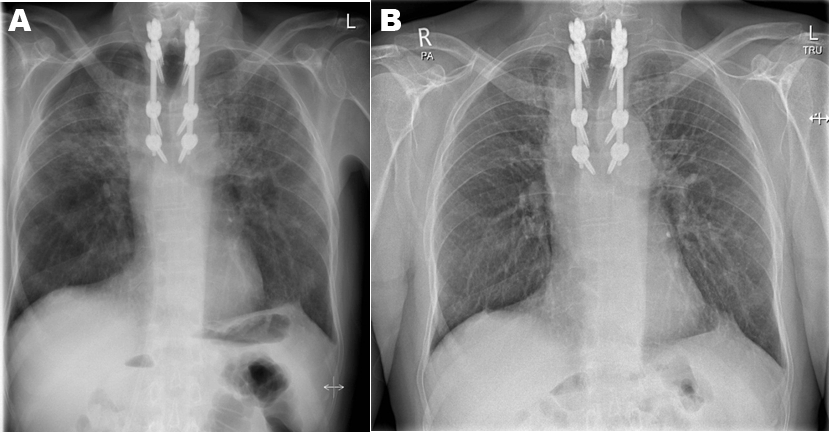

The patient presented to secondary care within eight weeks of completing thoracic radiotherapy complaining of worsening dyspnoea on exertion. On admission blood results showed WCC 6 x109/L, CRP 88 mg/L and Hb 120 g/L. Arterial blood gas analysis confirmed hypoxemic respiratory failure with pH 7.47, PCO2 4.38, PO2 8.5 and HCO3 26.2. CT scan of the thorax demonstrated bilateral small to moderate sized pneumothoraces, bilateral patchy ground glass opacification suggestive of radiation pneumonitis, septal thickening and atelectasis (Figure 1.) The patient was initiated on a tapering course of systemic corticosteroid therapy starting at 60 mg of prednisolone. This led to a rapid improvement clinically, in oxygenation and in chest radiograph appearances Figure 2(A and B). The pneumothoraces were observed closely over time and required no intervention. A chest radiograph performed six weeks post completion of treatment revealed complete re-expansion of both lungs and no evidence of fibrosis.

Figure 1: Computed Tomography scan demonstrating radiation pneumonitis and bilateral pnuemothoraces.